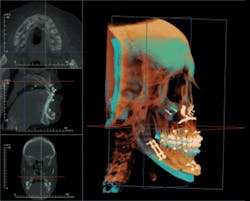

The Anatomage software employs various methods to filter out metallic scatter, producing a highly selective, clean 3-D volume in which structures can be easily selected and isolated for analysis. This process of clean isolation permits views of teeth, airway, temporomandibular condyles, the mandibular complex, and sinuses. Furthermore, it allows volumetric measurement and positional manipulation to formulate surgical or prosthetic projections.

Any structure that can be imaged can be rendered as a 3-D stereolithic model, which can be manufactured with SLA 3D printers. This capability allows surgeons to pre-plan surgeries such as joint replacement surgeries or major facial reconstructions on tabletop models. Bone plates can be preformed, implants selected, templates made for graft sizing, hands-on manipulation done for mock surgery, and arch bar and surgical stents fabricated.